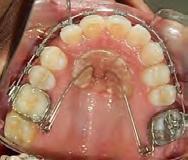

Las fotografías nos muestran en la Figura 2, la aparatología que se utilizó en el tratamiento que ella no terminó. La mordida abierta anterior de 1.5 mm, en la de frente las líneas medias no coincidentes, la clase III canina y molar izquierda, ausencia del canino 13 y del molar 46; en la Figura 3 el botón de Nance, algunos espacios en las arcadas.

Figura 3. Oclusal superior e inferior. Figura 4. Radiografía lateral de cráneo de inicio.